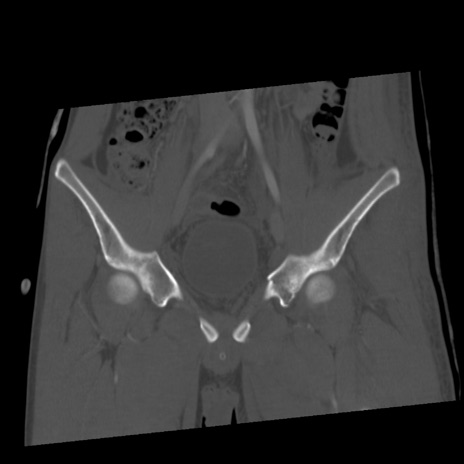

症例40 骨盤CT(冠状断像)

【症例】20歳代男性

【主訴】骨盤骨折

【現病歴】3日前にスノーボード中に木に衝突して受傷。遠方であり、当院紹介受診。

冠状断像